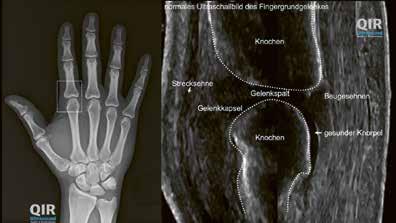

Sopra: articolazione metacarpofalangea sana in una radiografia (sinistra) ed ecografia (destra).

Sotto: articolazione metacarpofalangea colpita da AR in una radiografia (sinistra) ed ecografia (destra).

Esami complementari

In seguito, in genere la diagnosi viene verificata sulla base di esami di laboratorio, ecografie o radiografie. Tali esami hanno il fine di escludere altre patologie e valutare meglio la gravità e il probabile decorso dell’artrite reumatoide.

La presenza nell’emocromo di valori infiammatori elevati, del tipico fattore reumatoide e degli autoanticorpi (anticorpi anti­CCP) indica un’elevata attività della malattia

13 Aspetti medici

(ricaduta) e possibilmente un decorso con una prognosi peggiore. L’ecografia è volta a individuare l’ispessimento della membrana sinoviale, l’aumento del liquido sinoviale e dell’irrorazione sanguigna nell’articolazione nonché piccoli danni sulle ossa vicine all’articolazione. Questi piccoli punti danneggiati si chiamano erosioni. Le radiografie sono in grado di accertare se le mani e i piedi presentano erosioni e segni di osteoporosi, che viene favorita dai processi infiammatori. Al più tardi dopo un anno si effettua il confronto con lo stato precedente per verificare se la malattia è sotto controllo o se il trattamento va intensificato o modificato.